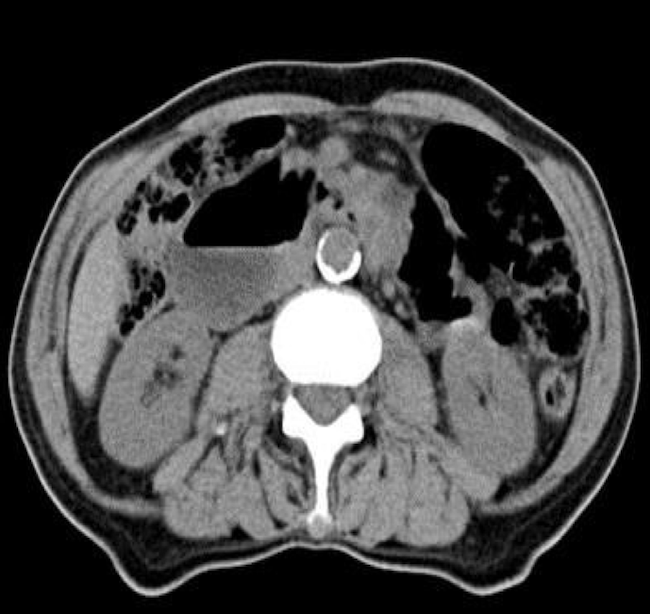

Findings of computed tomography (CT) scans of the abdomen (Figure 1) showed that the third portion of the duodenum had collapsed. The CT results created a greater need for further workup for small bowel obstruction. EGD and colonoscopy are unable to reach the third portion of the duodenum; thus, capsule endoscopy was performed, and the results of barium studies (Figure 2) revealed a duodenal stricture in the third portion with extension to the proximal jejunum. Push enteroscopy revealed adenocarcinoma of the duodenum. The patient agreed to undergo surgical removal of the cancerous lesions.

Figure 1. A transverse view of the small bowel obstruction on the initial CT that was later determined to be duodenal adenocarcinoma.